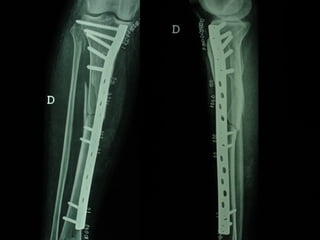

Dal Gennaio 2000 al Febbraio 2006 abbiamo trattato 167 fratture chiuse  con placca percutanea  in 164 pazienti :  27 lesioni diafisarie di gamba, 12 piloni tibiali ,  11 fratture prossimali di tibia, 36 fratture sovracondiloidee di femore, 17 fratture diafisarie di femore, 43 fratture metaepifisarie prossimali di omero, 21 diafisarie d’omero.  156 guarigioni 8 fallimenti

Dal Giugno 2002 al Dicembre 2004 abbiamo trattato 5 fratture esposte: 3 di tibia e 2 di ulna 5 guarigioni

I buoni risultati ottenuti dipendono da 5 punti fondamentali:   una accurata riduzione percutanea della frattura  precise vie di accesso  l’utilizzo della placca che consenta il più lungo braccio di leva possibile il pretensionamento della placca  una sintesi con un ridotto numero di viti

Precise vie di accesso

Placche lunghe e pretensionate

Placche lunghe e pretensionate Sintesi con un ridotto numero di viti